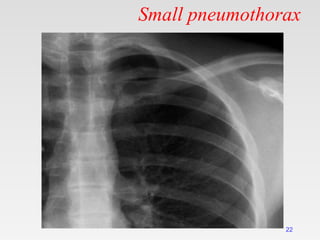

Small pneumothorax

22

23